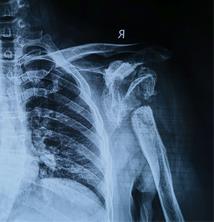

患者女,44岁,患者于入院前1月余出现右肩部间断疼痛不适,伴活动受限,偶有上肢皮肤麻木,局部皮肤完整,无擦伤及活动性出血,无肿胀,青紫及瘀斑,就诊于当地医院行肩关节影像检查示:右侧肱骨头坏死改变,右侧肩关节结构紊乱,正常结构消失,肱骨头缺血坏死样改变。

术前X线,肱骨头,肩关节盂缺损严重